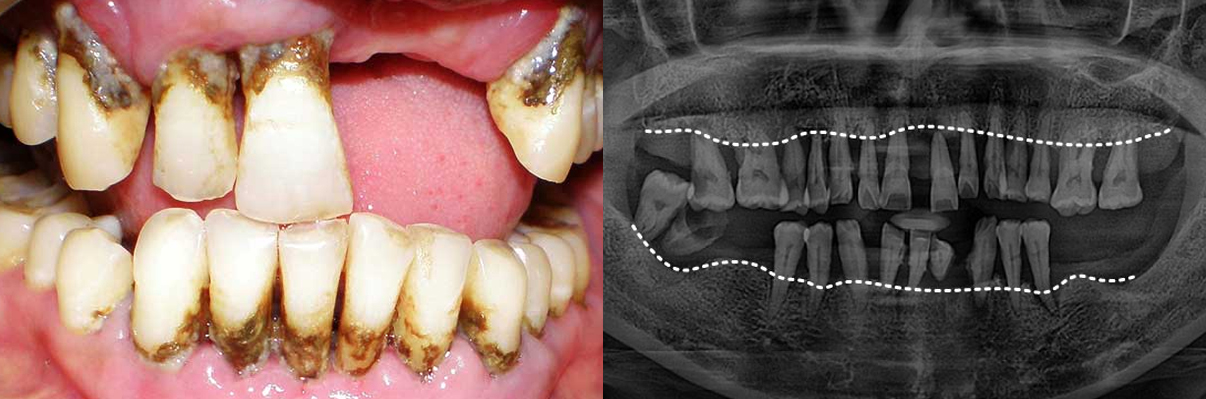

치주질환을 방치하면 뼈가 녹아내리며, 결국 발치에 이르게 됩니다. 잇몸이 무너진 후 치료는 더욱 어렵습니다.

겉으로 보기에도 치석과 염증이 심하며, 잇몸이 심하게 붓고 내려앉아 있습니다. 엑스레이에서는 뿌리의 절반 이상이 드러날 정도로 잇몸뼈가 심각하게 소실되어 있습니다.

치주질환 그대로 방치한다면

잇몸뼈까지 소실됩니다

치주질환을 방치하면 뼈가 녹아내리며, 결국 발치에 이르게 됩니다.

잇몸이 무너진 후 치료는 더욱 어렵습니다.